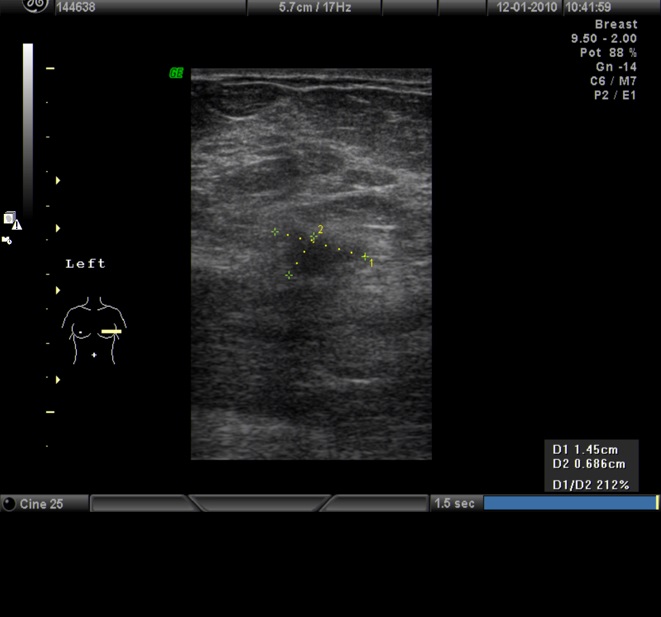

La prueba complementaria más útil tras la mamografía es la ecografía. Esta sirve sobre todo, para distinguir nódulos de carácter quístico, sólido o mixto.Además proporciona información muy valiosa sobre su estructura, morfología,, márgenes y orientación, sobre todo en mamas en donde la mamografía esta limitada, como es el caso de mamas densas.